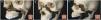

These are caused by a direct trauma to the malar process and are known as tetrapod fractures as they can involve four pillars delimited by sutures: frontozygomatic, zygomaticomaxillary, temprozygomatic and sphenozygomatic (Fig. 7).

(A) 3D representative of the pillars of the zygomaticomaxillary complex (ZMC) delimited by the frontozygomatic (purple), temporozygomatic (red), zygomaticomaxillary (green) and sphenozygomatic (yellow) sutures. (B and C) Axial and coronal computed tomography (CT) with a bone window. Zingg type B fracture of the ZMC; the zygomatic bone is free and displaced medially, reducing the orbital volume. (D–F) 3D reconstruction, axial and coronal CT with a bone window. Zingg type C ZMC fracture with involvement of the four pillars and comminution of the zygomatic bone.

With a view to surgical treatment, the Zingg classification divides them into three types31:

Zingg B: complete malar tetrapod fractures with a single free zygomatic bone fragment. Unstable and require internal fixation.

Zingg C: comminuted fractures. Always require surgical fixation.

(A) 3D representation of the mandibular units. Coronoid (Cr), condyle (Cd), ramus (R), angle (A), body (B), symphysis (S), alveolar process (Av) and basal segment (BS). (B and C) 3D reconstruction. Fracture of the occluding segment of the maxilla with dentoalveolar involvement and marked displacement of the fragments (asterisk). Fracture of the mandibular symphysis (arrow) and both condyles with impaction (arrow tips). (D) 3D reconstruction. Bilateral fracture of the body of the mandible with marked posterior displacement of the free fragment and risk of compromising the airway.